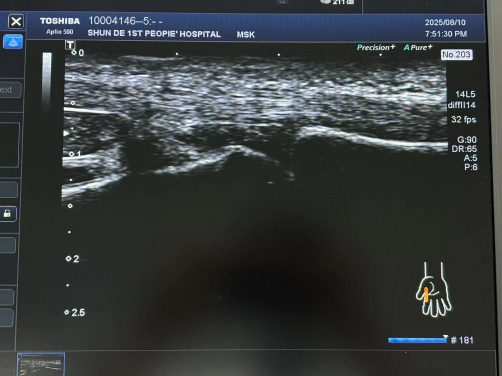

肌骨超聲引導(dǎo)下注射及針刀治療

肌骨超聲作為一種高分辨率的超聲成像技術(shù),具有無(wú)創(chuàng)、實(shí)時(shí)、動(dòng)態(tài)及可重復(fù)性高等優(yōu)點(diǎn),在評(píng)估關(guān)節(jié)及周圍軟組織病變方面具有獨(dú)特優(yōu)勢(shì)。能夠清晰顯示關(guān)節(jié)囊、滑膜、肌腱、韌帶等軟組織的細(xì)微結(jié)構(gòu)。

超聲實(shí)時(shí)引導(dǎo)下,PRP 注射可精準(zhǔn)進(jìn)入病變關(guān)節(jié),其激活后釋放的因子能促軟骨修復(fù)、抑炎止痛、改善功能;玻璃質(zhì)酸鈉注射可補(bǔ)充滑液、緩沖應(yīng)力、抑炎,保護(hù)修復(fù)軟骨。超聲引導(dǎo)下針刀微創(chuàng),可視動(dòng)態(tài),可實(shí)時(shí)調(diào)方案,減時(shí)、降并發(fā)癥、提療效。